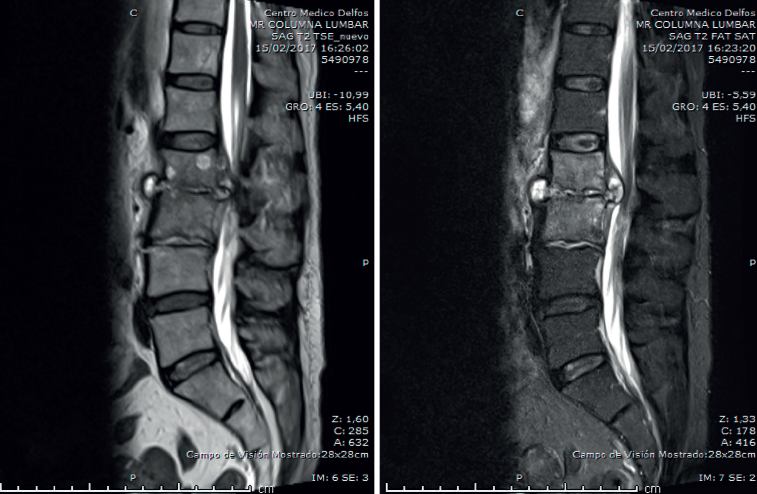

Figura 3. Radiografía a los 3 meses del ingreso inicial.

La analítica se había normalizado. En la radiografía lumbar (Figura 3) se veían signos de discopatía grave.